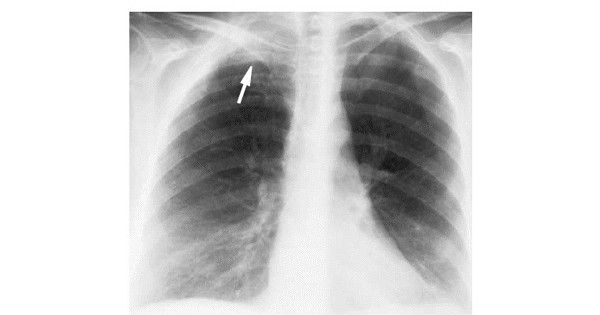

Рак пенкоста

Рак пенкоста 117 фотографий